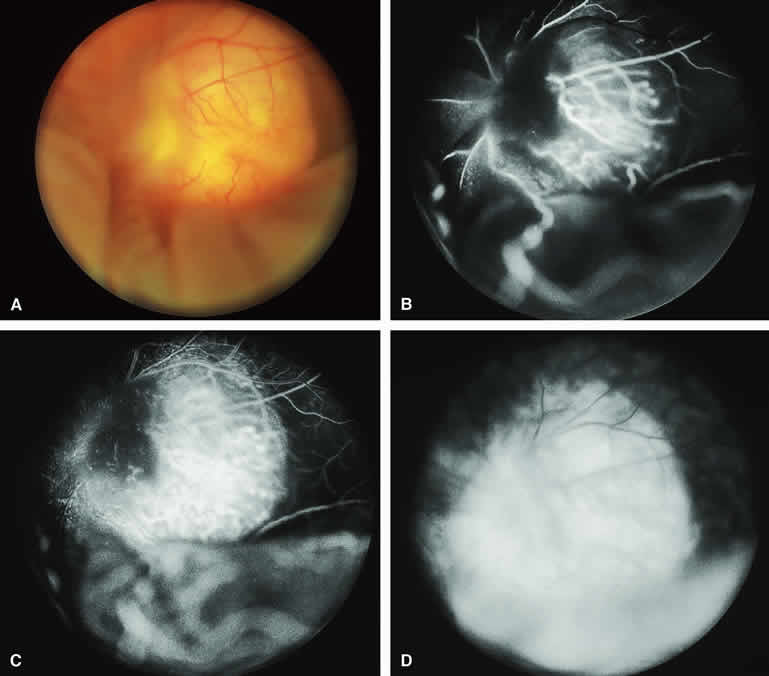

RETINAL CAPILLARY HEMANGIOMA (VON HIPPEL TUMOR)

The typical retinal capillary hemangioma is distinctive in its ophthalmoscopic appearance. The lesion is characteristically red-orange and associated with prominent afferent and efferent retinal vessels (Figs. 32A and 33A). Fluorescein angiography of these tumors has been described by multiple authors.1, 2, 3, 36, 37

Fig. 32. Small retinal capillary hemangioma. A. Spherical red vascular lesion in superotemporal periphery associated with prominent dilated, tortuous afferent and efferent retinal vascular channels. B-D. Fluorescein angiogram of lesion. B. Arterial phase frame showing filling of afferent arterial channel and lesion. C. Venous phase frame showing intense hyperfluorescence of vascular lesion, as well as complete filling of both afferent and efferent channels. D. Late-phase frame showing smudgy hyperfluorescence of lesion resulting from leakage of fluorescein into overlying vitreous and surrounding retina. Hypofluorescent and hyperfluorescent lesion at top of figure is site of a previously coagulated retinal capillary hemangioma.

Fig. 33. Larger retinal capillary hemangioma. A. Spherical pale red retinal lesion associated with dilated tortuous retinal arteries and veins and macular subretinal exudates. B-D. Fluorescein angiogram of lesion. B. Arterial phase frame showing dilation and tortuosity of feeding retinal artery and early hyperfluorescent filling of the vascular lesion. C. Venous phase frame showing intense hyperfluorescence of entire lesion plus fluorescein filling of the previously unfilled draining retinal vein. D. Late-phase frame showing smudgy leakage of fluorescein from the persistently hyperfluorescent retinal vascular lesion.

If fluorescein angiography is performed on a typical retinal capillary hemangioma (see Figs. 32B, C, and D and 33B, C, and D), it shows rapid filling of the afferent artery, brisk filling of the entire retinal vascular lesion, and intense hyperfluorescence of the entire vascular lesion shortly thereafter, followed by rapid filling of the efferent vessel. Retinal capillary hemangiomas characteristically leak fluorescein exuberantly into the overlying vitreous, so that the lesion's margins appear fuzzy in the late-phase frames. Because many retinal capillary hemangiomas are also associated with exudative subretinal fluid, the fluorescein commonly accumulates in the subretinal space by the late frames.

In patients with a relatively large peripheral retinal capillary hemangioma (Fig. 34A), the retinal arteries leading from the optic disc to the tumor and the retinal veins leading back from the tumor to the optic disc typically appear enormously dilated and markedly tortuous. On fluorescein angiography (see Fig. 34B, C, and D), the feeding artery tends to fill rapidly and the draining retinal vein similarly fills shortly thereafter. The peripheral retinal capillary hemangioma tends to become intensely hyperfluorescent with profuse leakage of fluorescein into the adjacent vitreous.

Fig. 34. Relatively large peripheral retinal capillary hemangioma associated with subtotal tractional-exudative retinal detachment. A. Prominent red to white peripheral fundus lesion superotemporally associated with tractional-exudative retinal detachment. B-D. Fluorescein angiogram of lesion. B. Early laminar venous phase frame of posterior pole showing massive dilation and tortuosity of fluorescein-filled superotemporal branch retinal artery and unfilled superotemporal branch retinal vein. C. Venous phase frame of posterior pole showing fluorescein filling of both the superotemporal branch retinal artery and vein. D. Venous phase frame showing diffusely hyperfluorescent peripheral retinal lesion.